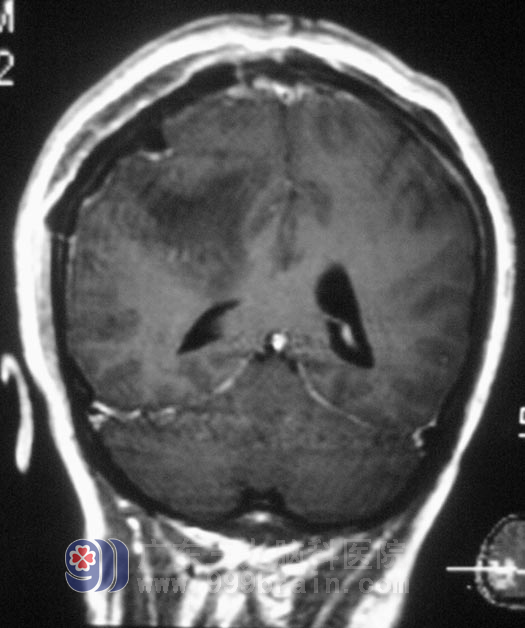

在广东三九脑科医院进一步检查,头颅MR检查提示右侧额顶部占位性病变,大小约4.3cm×4.2cm×2.2cm,考虑脑膜瘤。综合神经外科 鲁明主任为王女士在全麻下行右侧额顶部脑膜瘤切除术,术中切开硬脑膜后,显微镜下见肿瘤与硬膜粘连紧密,位于额顶部,肿瘤部分呈灰白色,质地、血运一般,与脑组织边界较清,予肿瘤全切。术后王女士没有出现肢体偏瘫等不良并发症。术后经病理证实为:合体型脑膜瘤。

▲手术后